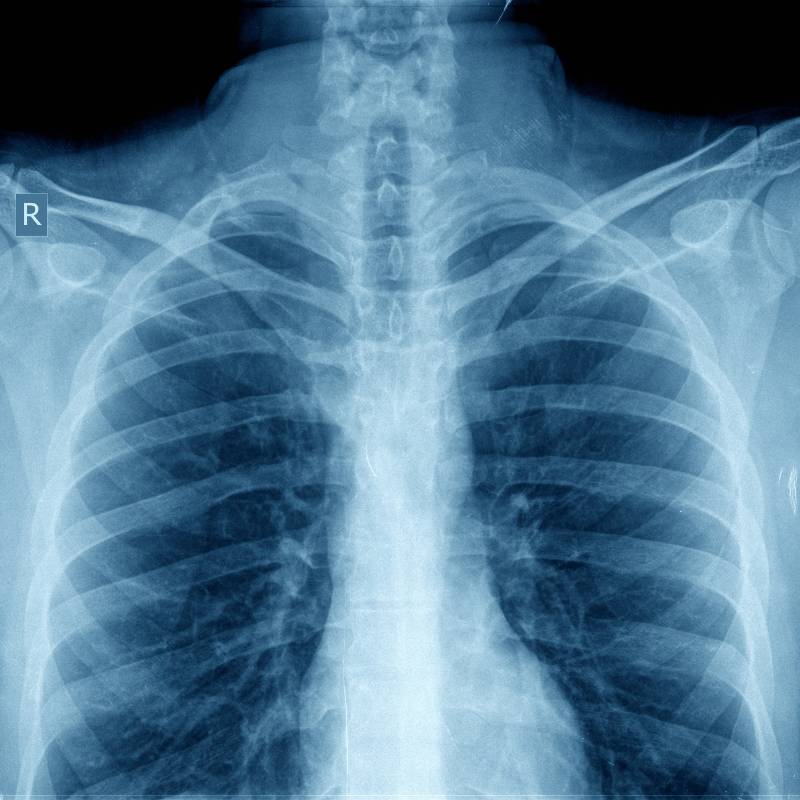

X-Ray dada digunakan untuk memeriksa keadaan paru-paru, jantung, dan struktur lain dalam kawasan dada, termasuk mengesan pneumonia, kegagalan jantung, dan ketumbuhan.

Sinar-X untuk mengesan masalah paru-paru dan jantung.